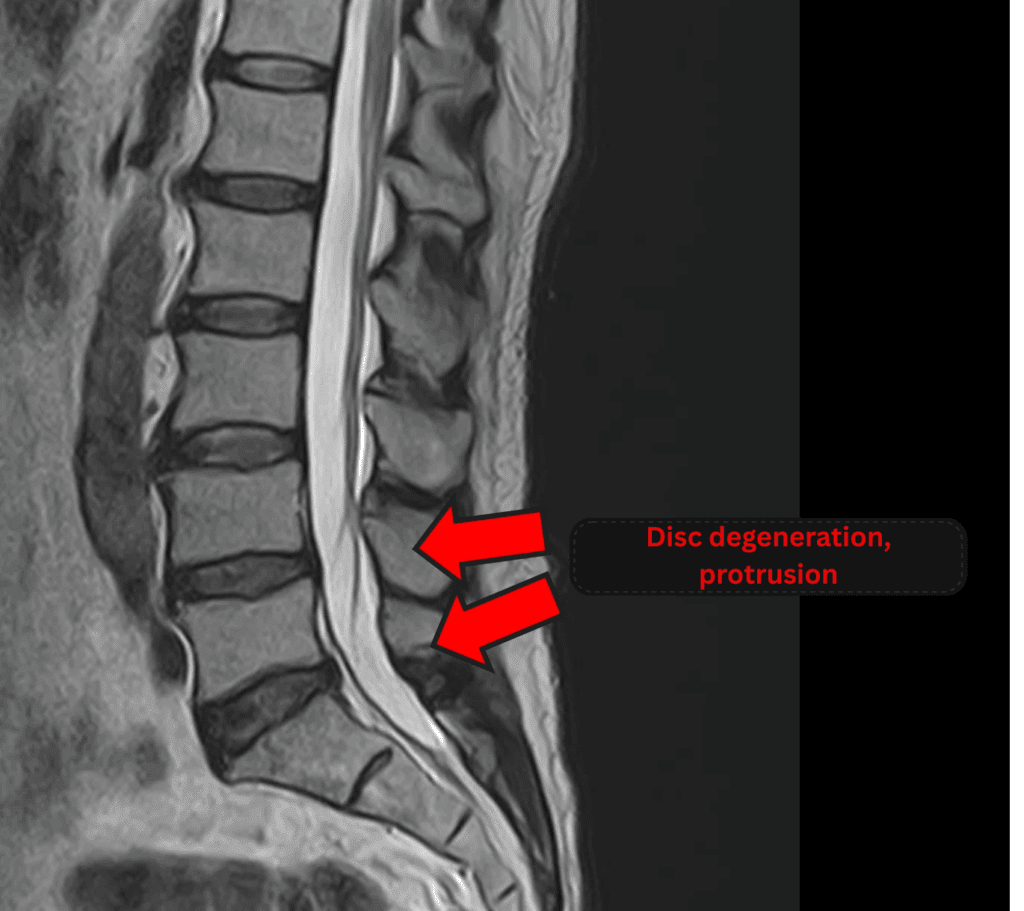

Imaging and findings

- L4/5, L5/S: Disc Degeneration and Bulging

The above findings were also observed on the imaging.

Compression of the spinal canal due to disc degeneration at L4/5 and L5/S is highly likely to be the cause of symptoms.